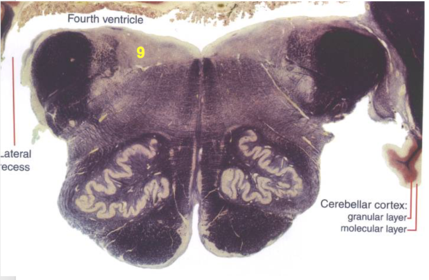

| Interposed nuclei | |

| Medial longitudinal fasciculus | |

| Facial nerve root - internal genu | |

| Abducens nucleus | |

| Lateral vestibular nucleus | |

| Superior vestibular nucleus | |

| Inferior cerebellar peduncle | |

| Superior cerebellar peduncle | |

| Dentate nucleus | |

| Fastigial nucleus | |

| Anterior spinocerebellar tract | |

| Spinal nucleus of V | |

| Spinal tract of V | |

| Middle cerebellar peduncle | |

| Medial lemniscus | |

| Trapezoid body | |

| Ventral trigeminothalamic tract | |

| Superior olive | |

| Longitudinal pontine fibers (corticospinal tract) | |

| Transverse pontine fibers (dark fibers) | |

| Pontine nuclei (pale) | |

| Central tegmental tract | |

| ALS | |